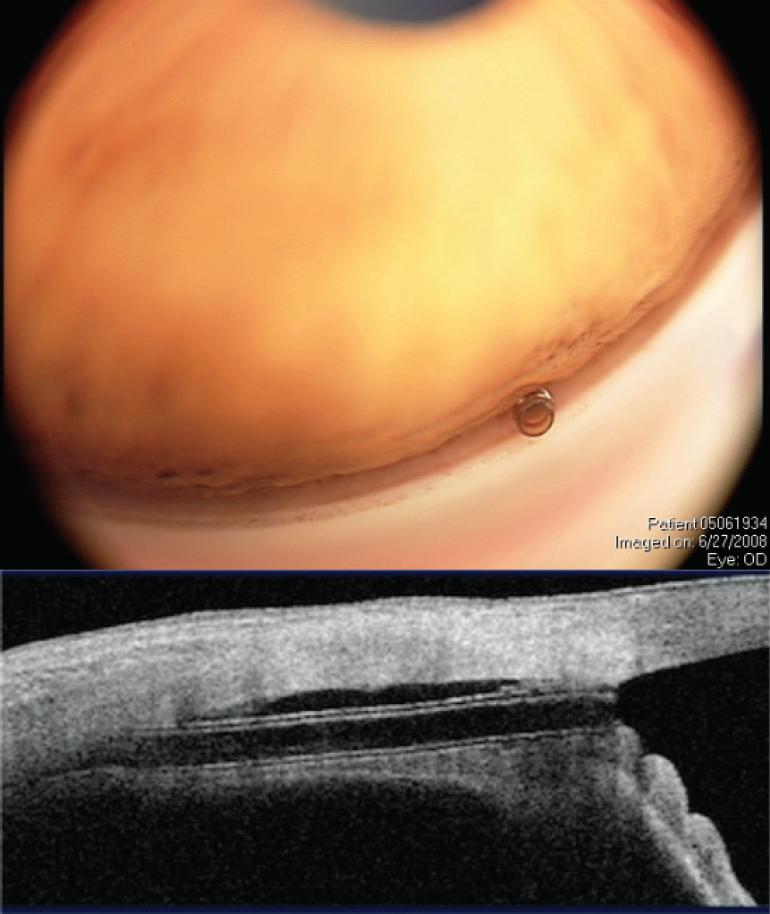

The CyPass Micro-Stent, due to its stiffness and positioning in the supraciliary space, follows the curvature of the inner sclera and assumes a more vertical orientation in the angle, and thus it is located closer to the peripheral cornea (Figure 6). If the device is placed too anteriorly or migrates, it may come into contact with the cornea. On the other hand, if migration or malpositioning of the iStent or Hydrus occurs, these devices will follow the contour of the canal and remain far from the cornea (of note, migration has not been an issue with these devices). Theoretically, the concerns with CyPass are not the same as those for other canal-based procedures, although long-term data are needed.

Figure 6. The CyPass Micro-Stent with corresponding views in the angle and on anterior segment OCT. Note the ideal deeper position of the implant with the collar below Schwalbe’s line (and no rings present). Dimensions: overall length = 6.35 mm, outer diameter = 430 μm, and inner diameter = 300 μm.